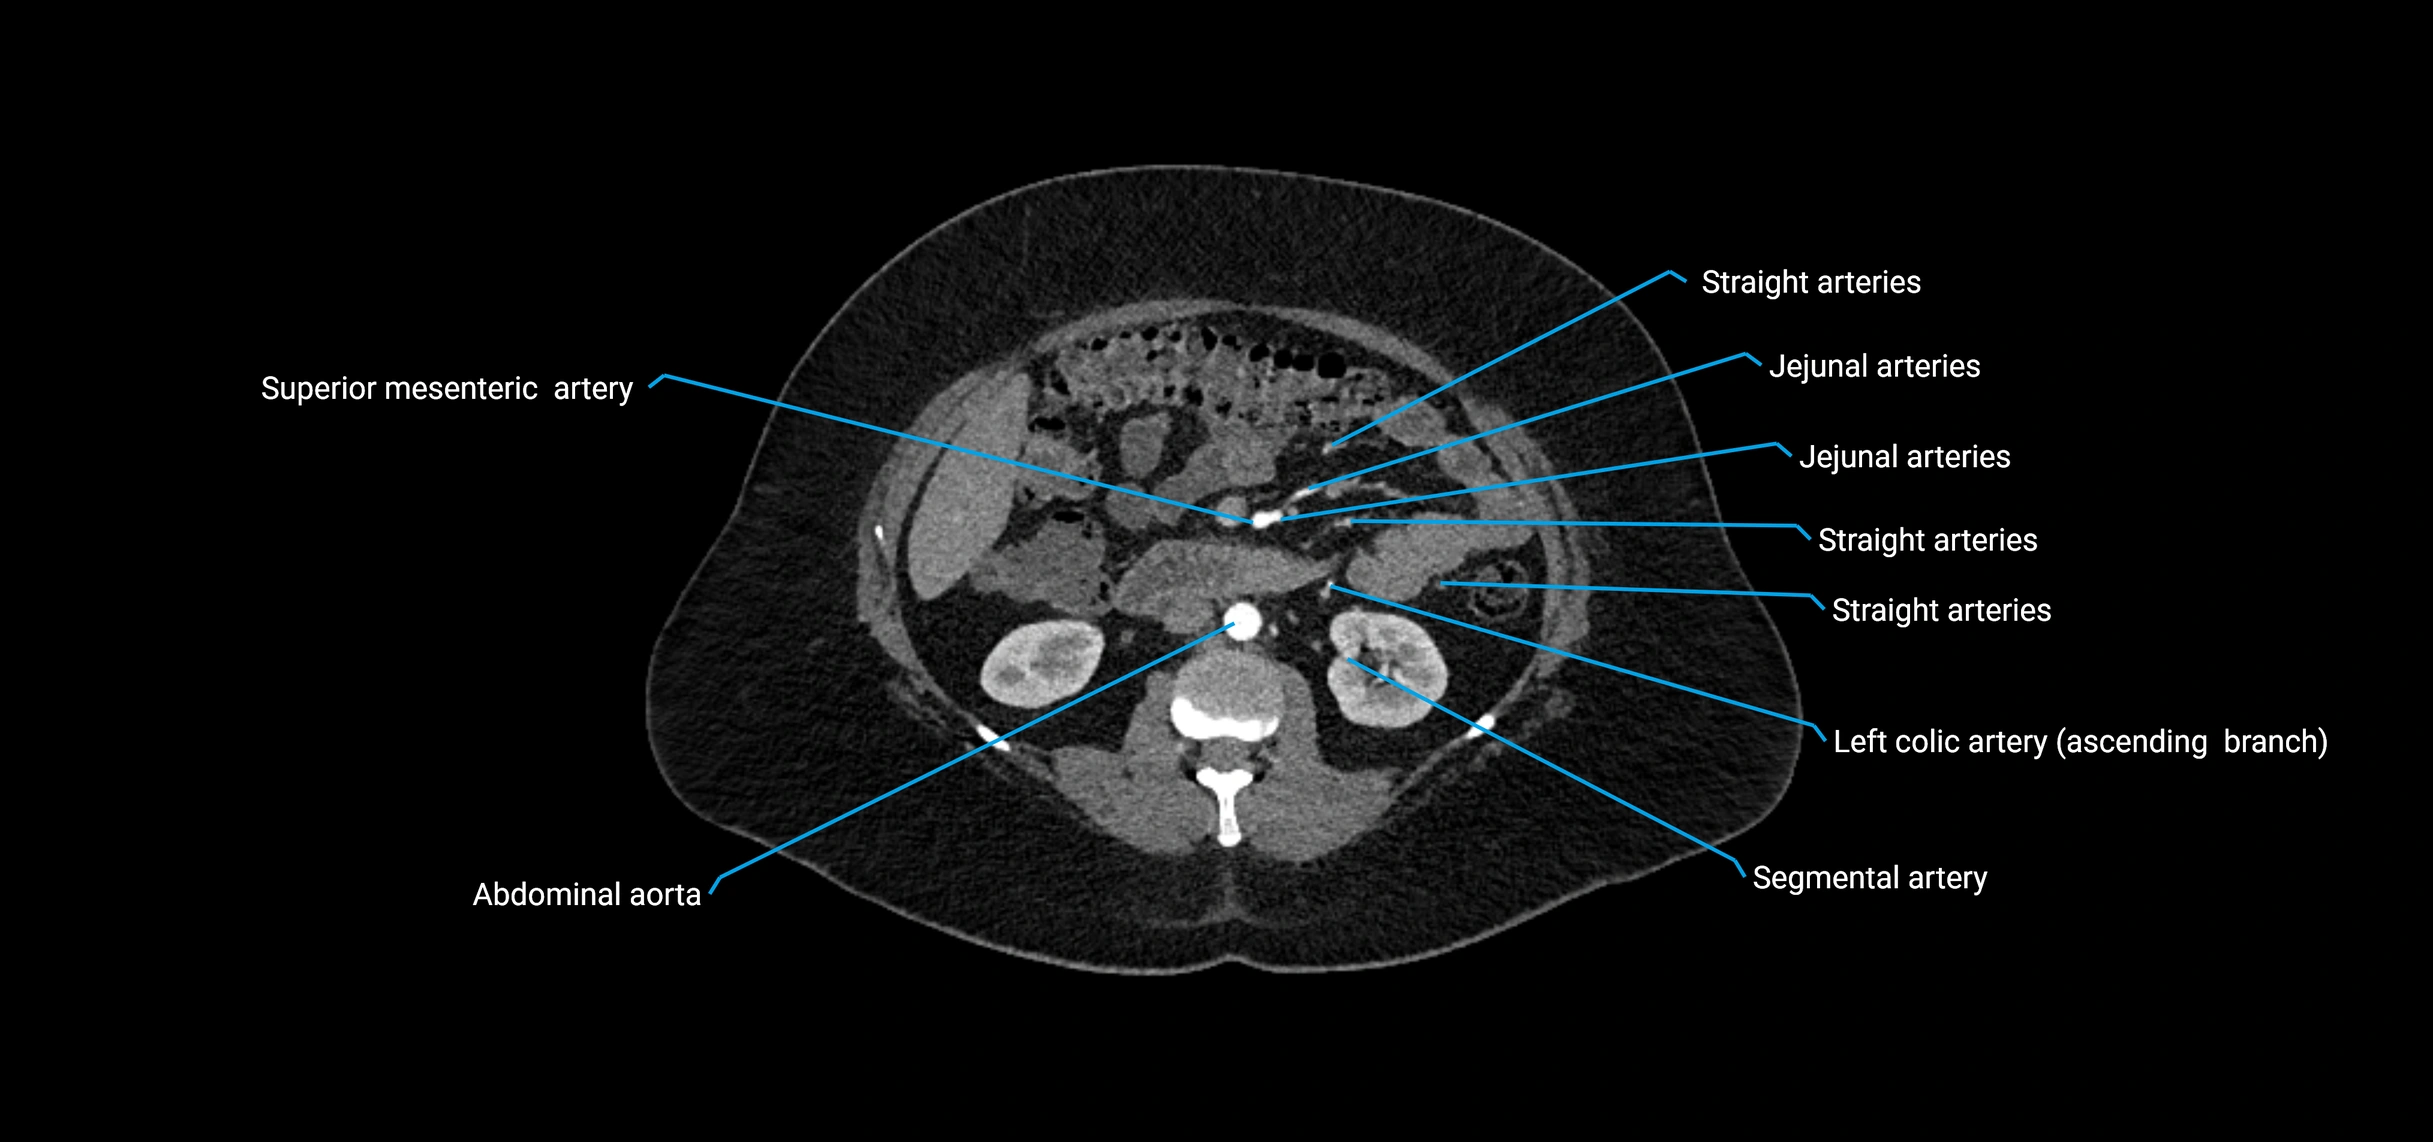

CT Appearance

Non-contrast CT:

• Appears as a tubular soft tissue structure anterior to vertebral bodies

• Calcified atherosclerotic plaques appear as hyperdense foci along the wall

• Useful for screening abdominal aortic aneurysm (AAA) size and mural calcification

Contrast-enhanced CT (CTA):

• Gold standard for abdominal aortic imaging

• Provides excellent detail of lumen, wall, aneurysm, thrombus, and branch vessels

• Multiplanar and 3D reconstructions help in aneurysm measurement, stent graft planning, and dissection evaluation

• Detects acute rupture, traumatic injury, or occlusion with high sensitivity